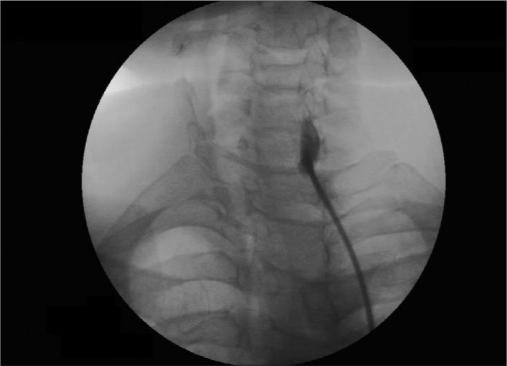

Stellate ganglion block (SGB) is very effective in management of chronic regional pain syndrome (CRPS-1). However, serious complication may occur due to accidental intravascular (intra-arterial) injection of local anaesthetic agents. Abdi and others, has suggested a modified technique in which fluoroscopy-guided block is given at the junction of uncinate process and body of vertebra at C7 level. In this approach vascular structures remain away from the trajectory of needle and thus avoid accidental vascular injection. We have used this technique of SGB in nine patients who were treated for CRPS-I. The blocks were effective in all the patients all the time without any vascular or other serious complication.

星状神经节阻滞(SGB)在慢性区域疼痛综合征(CRPS-1)的治疗中非常有效。然而,由于局部麻醉剂意外血管内(动脉内)注射,可能会发生严重并发症。阿卜迪等人提出了一种改良技术,即在C7水平的钩突与椎体交界处进行荧光透视引导下的阻滞。在这种方法中,血管结构远离针的轨迹,从而避免意外血管内注射。我们对9例接受CRPS-I治疗的患者使用了这种SGB技术。所有患者的阻滞始终有效,未出现任何血管或其他严重并发症。